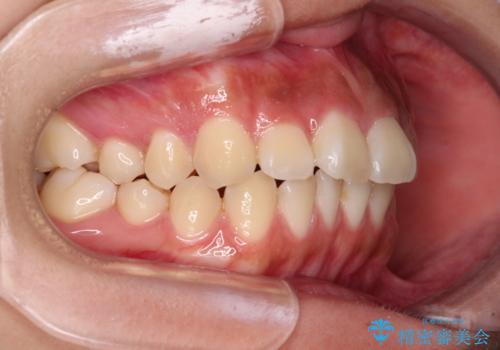

- 口元から飛び出てしまう前歯を気にして来院された患者様です。

上下前歯が嘴のように前方に突出しており、唇が閉じにくい状態であったため、上下左右の第一小臼歯4本を抜歯して、口元の突出感を改善することとしました。

目立たない装置を希望とのことで、上顎が裏側、下顎が表側のハーフリンガル装置を用いることとしました。